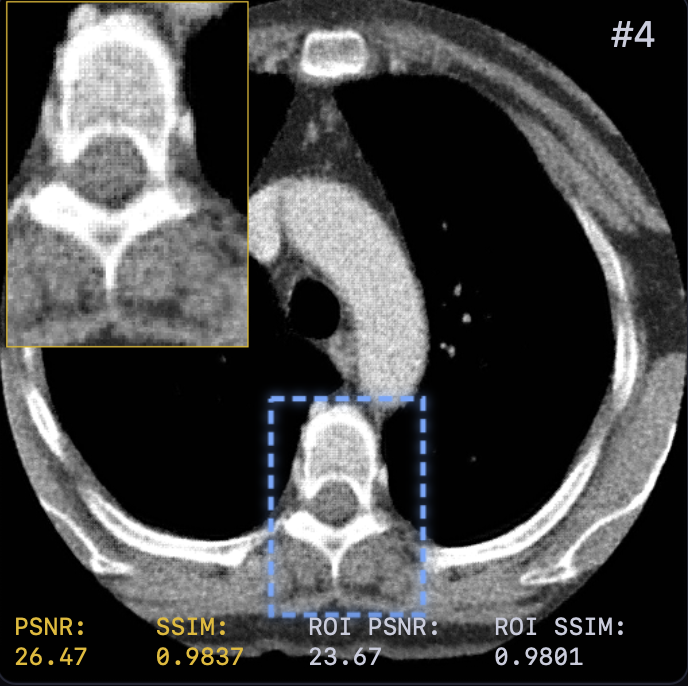

The reconstruction results are shown in Fig. 2. A zoomed-in region was extracted for a closer look with both PSNR and SSIM values attached. LTV preserves fine structures, such as vessel continuity, and reduces streak artifacts—critical for diagnostics—while avoiding the over-smoothing of TV or the anatomical inconsistencies of FBP+U-Net.